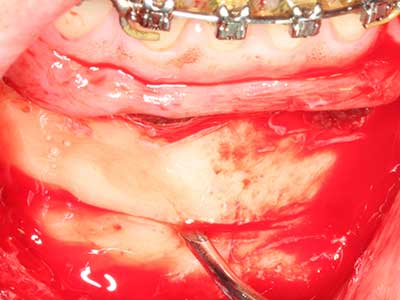

Piezo surgery has additional advantages when harvesting bone blocks. In addition to the high precision with osteotomy described above, the use of the thin saw tips specifically minimizes loss of material. Greater loss of material during harvesting can be expected with the thicker instrument tips, particularly when using Lindemann drills (Lakshmiganthan, Gokulanathan et al. 2012). The basal separation, which is necessary particularly for retromolar block transplants, is simplified by specially designed rectangular saws, with the result that piezo surgery is viewed as a precise, simple and safe procedure for harvesting retromolar bone blocks (Happe 2007) (Fig. 1-12).

Fig. 1: Preparation of a bone cover with the Piezomed (W&H Salzburg, Austria).

Fig. 3: Basal separation of the block is easier with specially angled attachments.